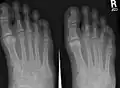

X-ray of foot, showing phalangeal fracture -